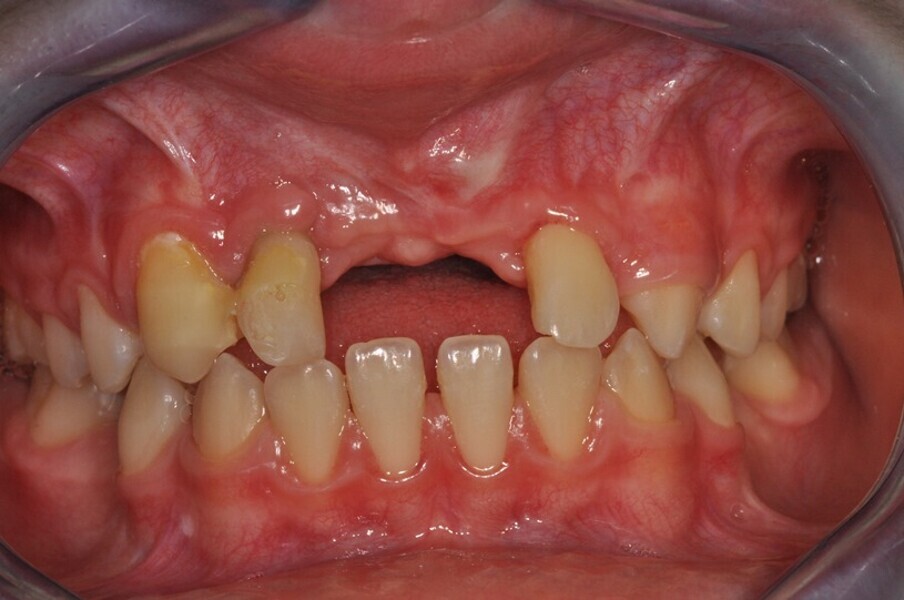

Ryc. 2_TK przedzabiegowe.